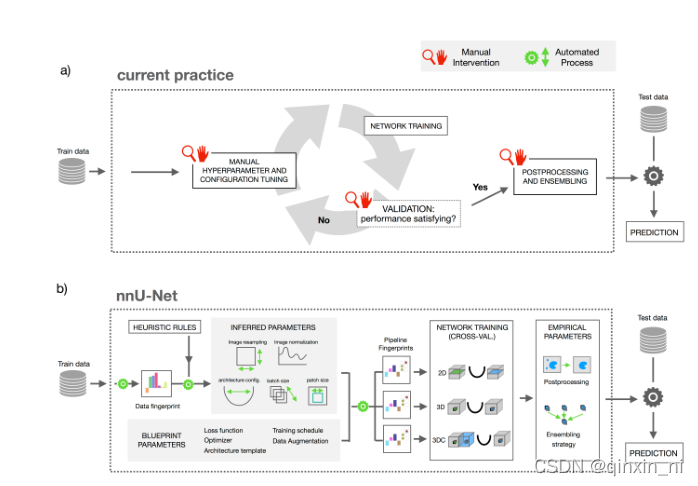

下图a代表了现在根据专家知识和实验修正的模型设计思路,针对于任务,

b代表nnUnet的设计思路,定义了dataset fingerprint和pipeline fingerprint。Dataset fingerprint是数据集的关键表征,比如图像大小、体素空间信息和类别比例;Pipeline fingerprint被分为三组:blueprint、inferred和empirical参数。Blueprint代表基本的架构设计,比如U-Net类的模板、损失函数、训练策略和数据增强;Inferd代表对新数据集的必要适应进行编码,并包括对确切的网络拓扑、补丁大小、批次大小和图像预处理的修改。数据指纹和inferd之间的关系是通过执行一组启发式规则建立的,当应用于看不见的数据集时,无需进行昂贵的重新优化。通过对训练案例进行交叉验证,可以自动确定empirical参数。默认情况下,nnU-Net会生成三种不同的U-Net配置:一个2D U-Net、一个以全图像分辨率运行的3D U-Net和一个3D U-Net级联。交叉验证后,nnU-Net会根据经验选择性能最佳的配置或整体。

1) 最近普遍的深度学习的步骤:进行迭代式的训练和调参,训练之后评估结果,效果不好则进行调参,调参之后继续训练,最终进行侦测,反复如此;

2) nnUNet:

1.数据【无论是训练数据还是测试数据,都具有相对应的属性,即指纹】的属性会被总结成一种“数据指纹”;

2.一系列的启发式的规则会推理出适合这种指纹的“管道”(由蓝图参数(计划参数)推理得出):

3.上一步推理出的参数,例如image resample、batch_size等,联合起来成为“管道指纹”:

4.2D、3D和3D_Cascaded三个网络分别训练,得出各自的模型(三个网络结构共享一个“管道指纹”,五折交叉验证)

5.选择出最优的模型进行推理(可以单个进行推理,也可以三个模型一起进行推理)

上图(a)展示了近来的多数医学图像分割是如何进行一个新的数据集的训练的。这个过程是“专家驱动”的,而且需要长时间的人为的试错的过程,显然,这样的训练方式对于手头上要处理的数据可能极少有先兆的参考。上图(b)中nnUNet却将这个自适应的过程系统化。

因此,我们在此定义了一个类似于“图片大小”这样的标准数据集的属性——dataset fingerprint(数据指纹),和一个pipeline fingerprint(管道指纹)[一个训练计划中各个配置的合体]。对于一个给定的“数据指纹”,nnUNet负责生成一个指定的“管道指纹”。

- 在nnUNet中,这些“管道指纹”被分为蓝图参数、推理参数和经验参数

- 蓝图参数:

- 基础的网络架构选择:比如一个朴素的nnUNet网络;

- 易于选择的一些表现较好的常用超参数:比如损失函数、训练进度表、数据增强方式;

- 推理参数

- 对一个新数据集进行适应性的编码,包括新的网络拓扑结构、patch_size、batch_size和图像预处理

- 数据指纹’和‘管道指纹’两者之间的关系可以通过执行一系列启发式的规则来进行建立,而且遇到未知的数据集时也不需要昂贵的反复训练的代价;

- 注意许多的设计选择都是相互依赖的

- nnUNet卸去了人为解释这些依赖关系的压力

- 经验参数:经验参数只会在后面的推理时使用,这点从上图b可以看出

- 2D、3D、3D-cascade

- 2D-Unet: 普通的2D-Unet

- 3D-Unet: 对一整张图片像素进行操作

- 3D-cascade: 级联网络:第一个网络对下采样图片进行操作,而第二个网络对前一个网络产生的结果在整个图片的像素上进行调整。

- 在进行完交叉验证之后,nnUNet会经验性的选择表现最好的参数,可能是独个的推理结果,也可能是一起推理的结果。在结果可以评估的情况下,把对次优效果的抑制作为一项后处理操作。